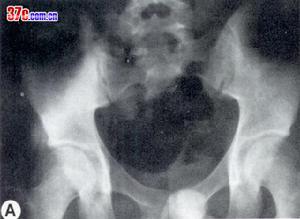

骶髂關節結核--X片3.髂外動脈搏動引起的骨質缺失:

近髂外動脈區的局限性骶髂關節結核有時需與髂外動脈搏動引起的骨質破壞或缺失鑑別,前者引起的骨質破壞區雖比較局限,但骨質破壞較廣泛,破壞區邊緣不清,無硬化;而髂外動脈長期搏動可引起髂骨下緣較明顯而深的凹陷,並可見凹陷的邊緣清楚,無硬化徵象。另外本病還需注意與骶髂勞損,椎間盤突出症,腰椎結核和髖關節炎症等鑑別。

X線攝片早期關節面模糊,邊緣糜爛,關節間隙增寬,晚期關節間隙變窄。並有竇道,常繼發感染。關節呈現硬化。關節破壞嚴重者同側髂骨和恥骨可上移發生病理脫位。